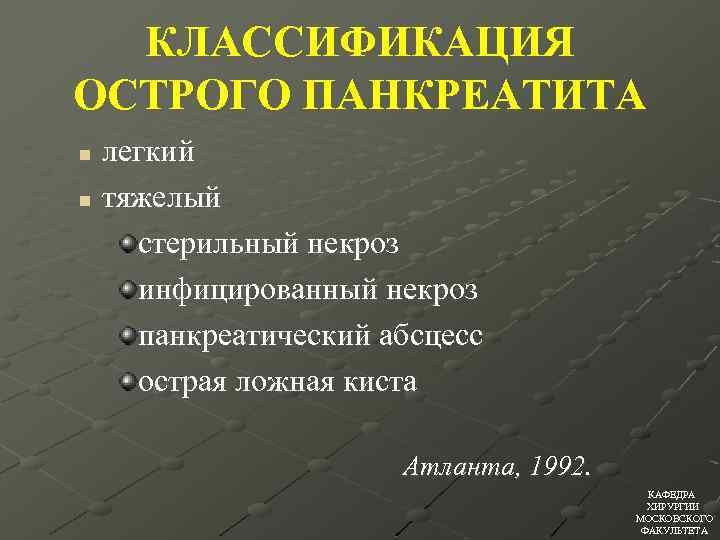

КЛАССИФИКАЦИЯ ОСТРОГО ПАНКРЕАТИТА легкий n тяжелый стерильный некроз инфицированный некроз панкреатический абсцесс острая ложная киста n Атланта, 1992. КАФЕДРА ХИРУРГИИ МОСКОВСКОГО ФАКУЛЬТЕТА

КЛАССИФИКАЦИЯ ОСТРОГО ПАНКРЕАТИТА легкий n тяжелый стерильный некроз инфицированный некроз панкреатический абсцесс острая ложная киста n Атланта, 1992. КАФЕДРА ХИРУРГИИ МОСКОВСКОГО ФАКУЛЬТЕТА